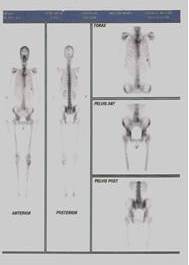

Se solicitan estudios de extensión: tomografía axial computarizada de abdomen y pelvis 15/07/2008: no demuestra imágenes de tipo MT a nivel hepático. No se demostraron adenopatías. Aparente aumento de volumen del cuello uterino en relación al cuerpo uterino que es relativamente pequeño. No se puede evaluar con definición el recto por encontrarse muy distendido al momento del estudio (Figura 3).